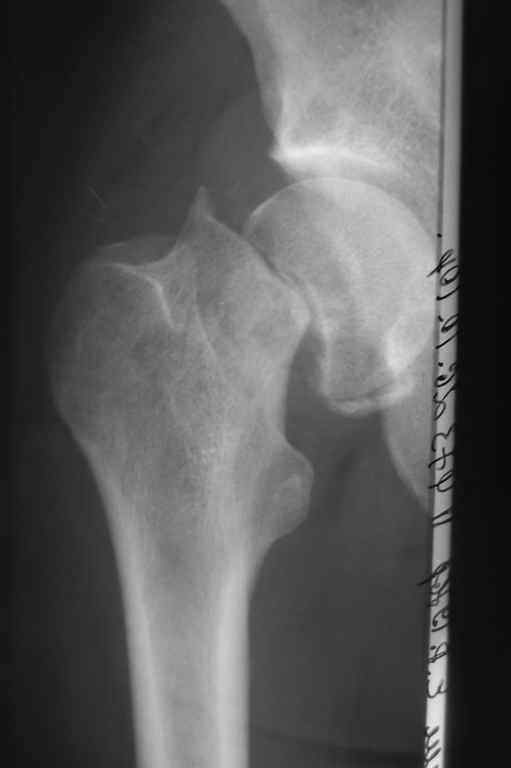

Пациенту 34 года. Травма 10 недель назад.

Стоит ли попробовать выполнить остеосинтез, либо сразу - эндопротезирование?